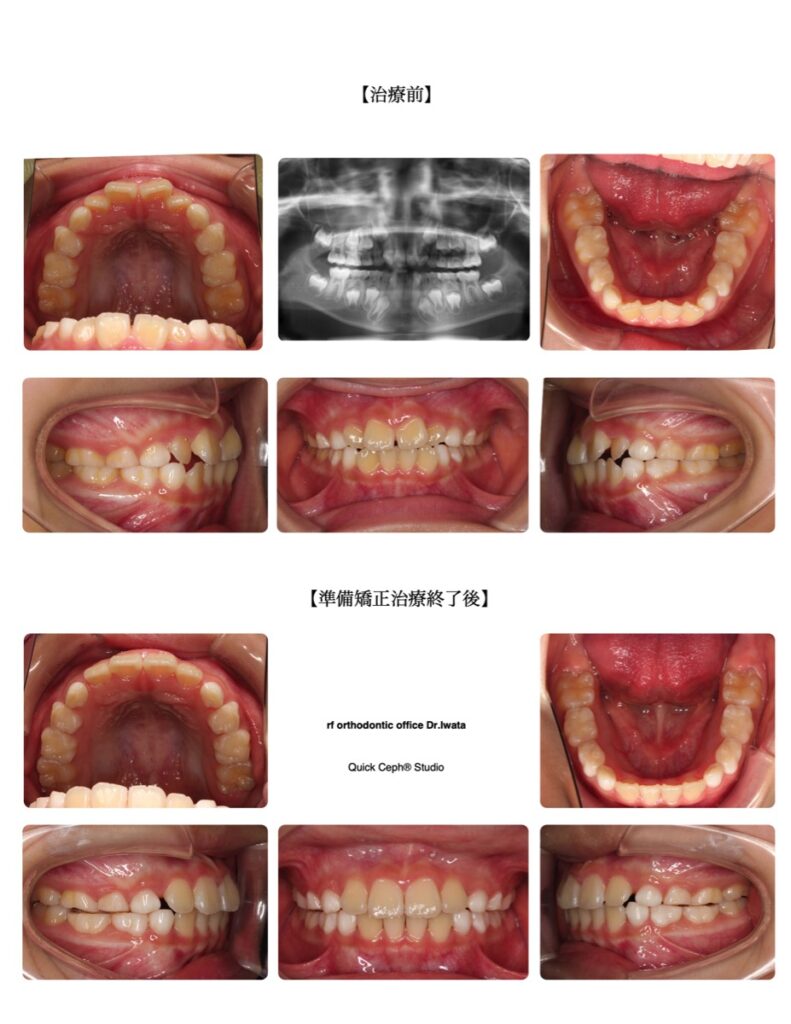

叢生症例 <上顎前歯翼状捻転を伴う叢生に対する準備矯正治療>

【主訴】上下の前歯がガタガタに生えてきた。特に上の前歯がハの字になってきて今後の歯並びが心配。

【主な症状】叢生(上顎前歯部翼状捻転含む)